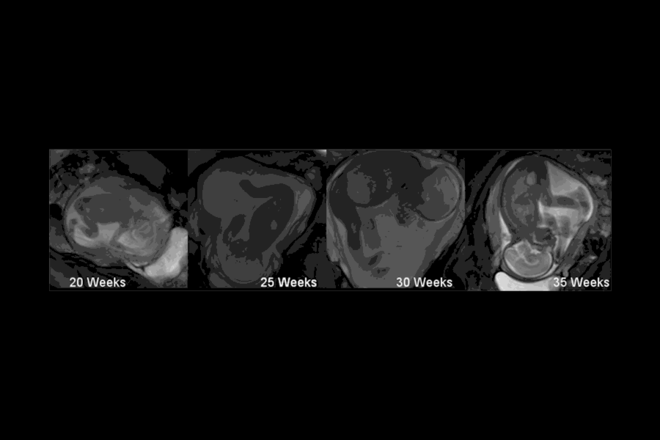

▪ Lëvizjet e bebes në stomak fillojnë shumë përpara se t'i ndieni ato. Të vegjlit në barkun e nënës së tyre fillojnë të bëjnë lëvizjet e para që në javën e nëntë, por më pas kanë vend të mjaftueshëm në stomak, ndaj nuk e ndjejnë fare.